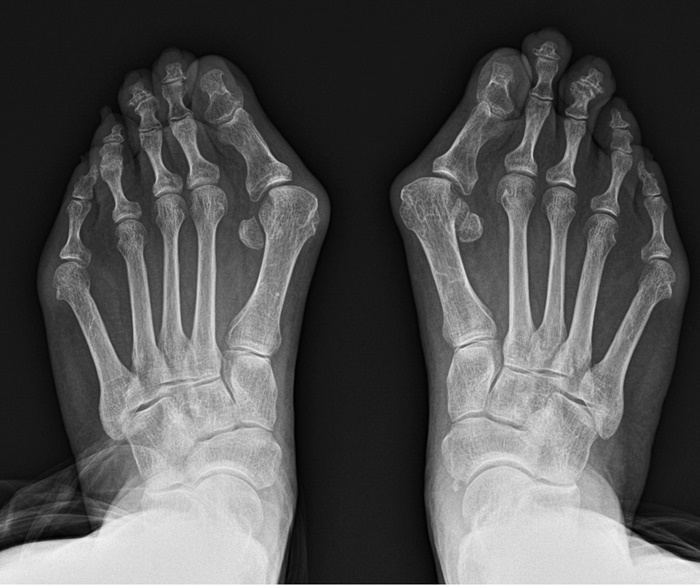

![]() |

| ¹«Áö¿Ü¹ÝÁõ ȯÀÚÀÇ X-Ray »çÁø. /»çÁøÁ¦°ø=¿¬¼¼°Ç¿ìº´¿ø |